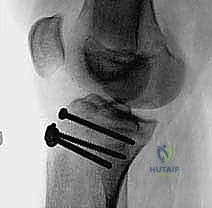

2. التصوير بالأشعة السينية (X-Rays)

هو الخطوة التشخيصية الأساسية. يتم أخذ صور من زوايا متعددة (أمامية خلفية AP، وجانبية Lateral). الصورة الجانبية هي الأكثر أهمية لأنها تظهر بوضوح مدى انفصال (انزياح) حدبة الظنبوب عن مكانها الطبيعي، وتظهر أيضاً ارتفاع الرضفة (Patella Alta).

5. التثبيت الداخلي (Internal Fixation)

هنا تبرز مهارة الجراح في اختيار طريقة التثبيت التي لا تضر بصفيحة النمو (إذا كانت لا تزال مفتوحة).

* استخدام البراغي المجوفة (Cannulated Screws): يتم إدخال سلك توجيهي رفيع أولاً، وبعد التأكد من موقعه بالأشعة السينية داخل غرفة العمليات، يتم إدخال برغي أو برغيين من التيتانيوم القوي فوق السلك لتثبيت العظم. يحرص الدكتور هطيف على توجيه البراغي من الأمام إلى الخلف، وفي بعض الأحيان بزاوية مائلة لتجنب اختراق صفيحة النمو قدر الإمكان.